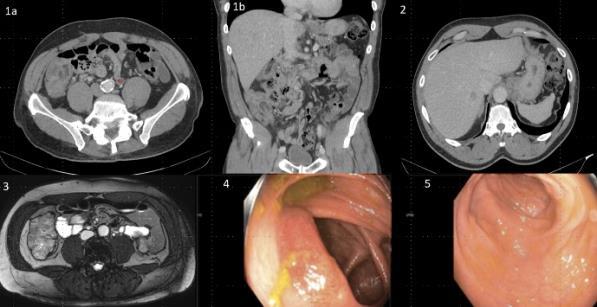

CASE REPORT/CLINICAL REVIEW/CLINICAL VIGNETTE GASTROENTEROLOGY/HEMATOLOGY/ONCOLOGY

PANCREATIC NEUROENDOCRINE TUMOR PRESENTING AS AN ABDOMINAL PAIN FOLLOWING SUCCESSFUL HELICOBACTER PYLORI ERADICATION

Omar Belfaqeeh1 , Frederick

Rozenshteyn1

Bruce Gelman1

,

1Mount Sinai Morningside-West Hospitals, Icahn School of Medicine at Mount Sinai, New York, NY, United States

BACKGROUND/INTRODUCTION: Zollinger-Ellison syndrome (ZES) is caused by functional duodenal or pancreatic neuroendocrine tumors (NET) that secrete gastrin resulting in excess acid production causing peptic ulceration, reflux esophagitis and diarrhea. It is estimated that the annual incidence is one per million population, of which 20 to 30 percent are associated with multiple endocrine neoplasia type 1 (MEN1). Recent studies have demonstrated that 70-80% of gastrinomas arise in the duodenum.

CASE PRESENTATION: A 67-year-old male with a history of partial liver resection, peptic ulcer disease, and Helicobacter pylori gastritis s/p quadruple therapy presented with acute on chronic abdominal pain despite being on a proton pump inhibitor (PPI). He had abdominal pain for the past 5 years associated with nausea, vomiting, diarrhea, and a 50-pound unintentional weight loss. An esophagogastroduodenoscopy (EGD) six months ago demonstrated peptic ulcer disease and Helicobacter pylori which was successfully eradicated.

He underwent a CT-abdomen/pelvis with intravenous contrast in the emergency department which revealed an enhancing 3.4 cm mass in the head of the pancreas with retroperitoneal lymphadenopathy. MRI of the abdomen confirmed the presence of a 3.2 cm enhancing pancreatic head mass with direct extension into the second portion of the duodenum and multiple enlarged retroperitoneal lymph nodes. EGD was remarkable for edema and granularity in the first portion of the duodenum. Endoscopic ultrasound (EUS) was notable for a hypoechoic and heterogeneous irregular mass in the pancreatic head measuring 25 mm by 23 mm in maximal crosssectional diameter with invasion into the serosa and muscularis mucosa of the duodenum. Fine needle aspiration of the pancreatic mass for cytology revealed a well-differentiated pancreatic neuroendocrine tumor (Ki-67 index <1%). Gastrin levels were ordered. He presented again to the hospital 3 weeks later with worsening epigastric abdominal pain and nausea despite adhering to PPI therapy. CT-abdomen revealed new proximal duodenal ulcerations. Gastrin level from the prior admission was noted to be 1988 pg/mL. He subsequently underwent a Whipple's procedure with no complications and was discharged home with a planned EGD surveillance in 6 months.

CONCLUSION: Establishing a diagnosis of ZE can be difficult due to the lack of consistent diagnostic criteria, the widespread use of PPIs that masks mask the symptoms and limited access to gastric pH testing. In our case, the diagnosis was based on a fasting serum gastrin level, FNA results, and imaging findings. Owing to its variable clinical presentation, high mortality, and challenging primary lesion identification, clinicians should consider ZE in the differential diagnosis of patients who are symptomatic despite taking PPI, having Helicobacter pylori successfully eradicated or having multiple duodenal and gastric ulcers that fail to respond to therapy.

36

Figure 1: CT Abdomen and Pelvis with contrast showing a suspicious mass in the second portion of the duodenum/pancreatic head.